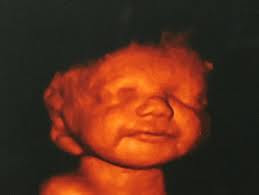

My Pregnancy Journey Pregnancy Check Up 9 Week 28 Week Herneenazir Com